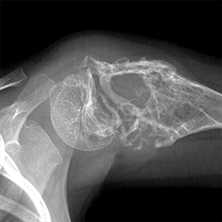

о Нейропатический акроостеолизис, может быть сильно выраженным и вовлекать большой объем костной ткани, помимо дистальных фаланг (20-70% случаев госпитализации)

о Остатки периферической кости могут иметь очень острый или тупой угол

о Нейрогенная артропатия лучезапястного или голеностопного сустава

о Периостит, остеомиелит (редко; 3-5% случаев госпитализации)